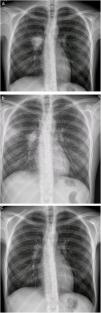

At 23 years of age, she presented a marked clinical deterioration, and the chest X-ray showed a right pulmonary mass that raised the differential diagnosis of several entities, including neoplastic diagnosis (Fig. 1a).

However, after eight weeks of antibiotherapy, she suffered a notorious clinical worsening: the X-ray showed new bilateral parenchymal infiltrates (Fig. 1b) and the lumbar MRI (severe pain), identified a subchondral osteitis in the soma of L4. These findings led to a suspected diagnosis of disseminated mycobacteriosis and IRIS, like that described in other series.4

Meropenem and dexamethasone (DXM) were added to the treatment, and she experienced gradual clinical and radiological improvement (Fig. 1c) until she was completely asymptomatic after 2 months of treatment, a situation that is still in place at present.